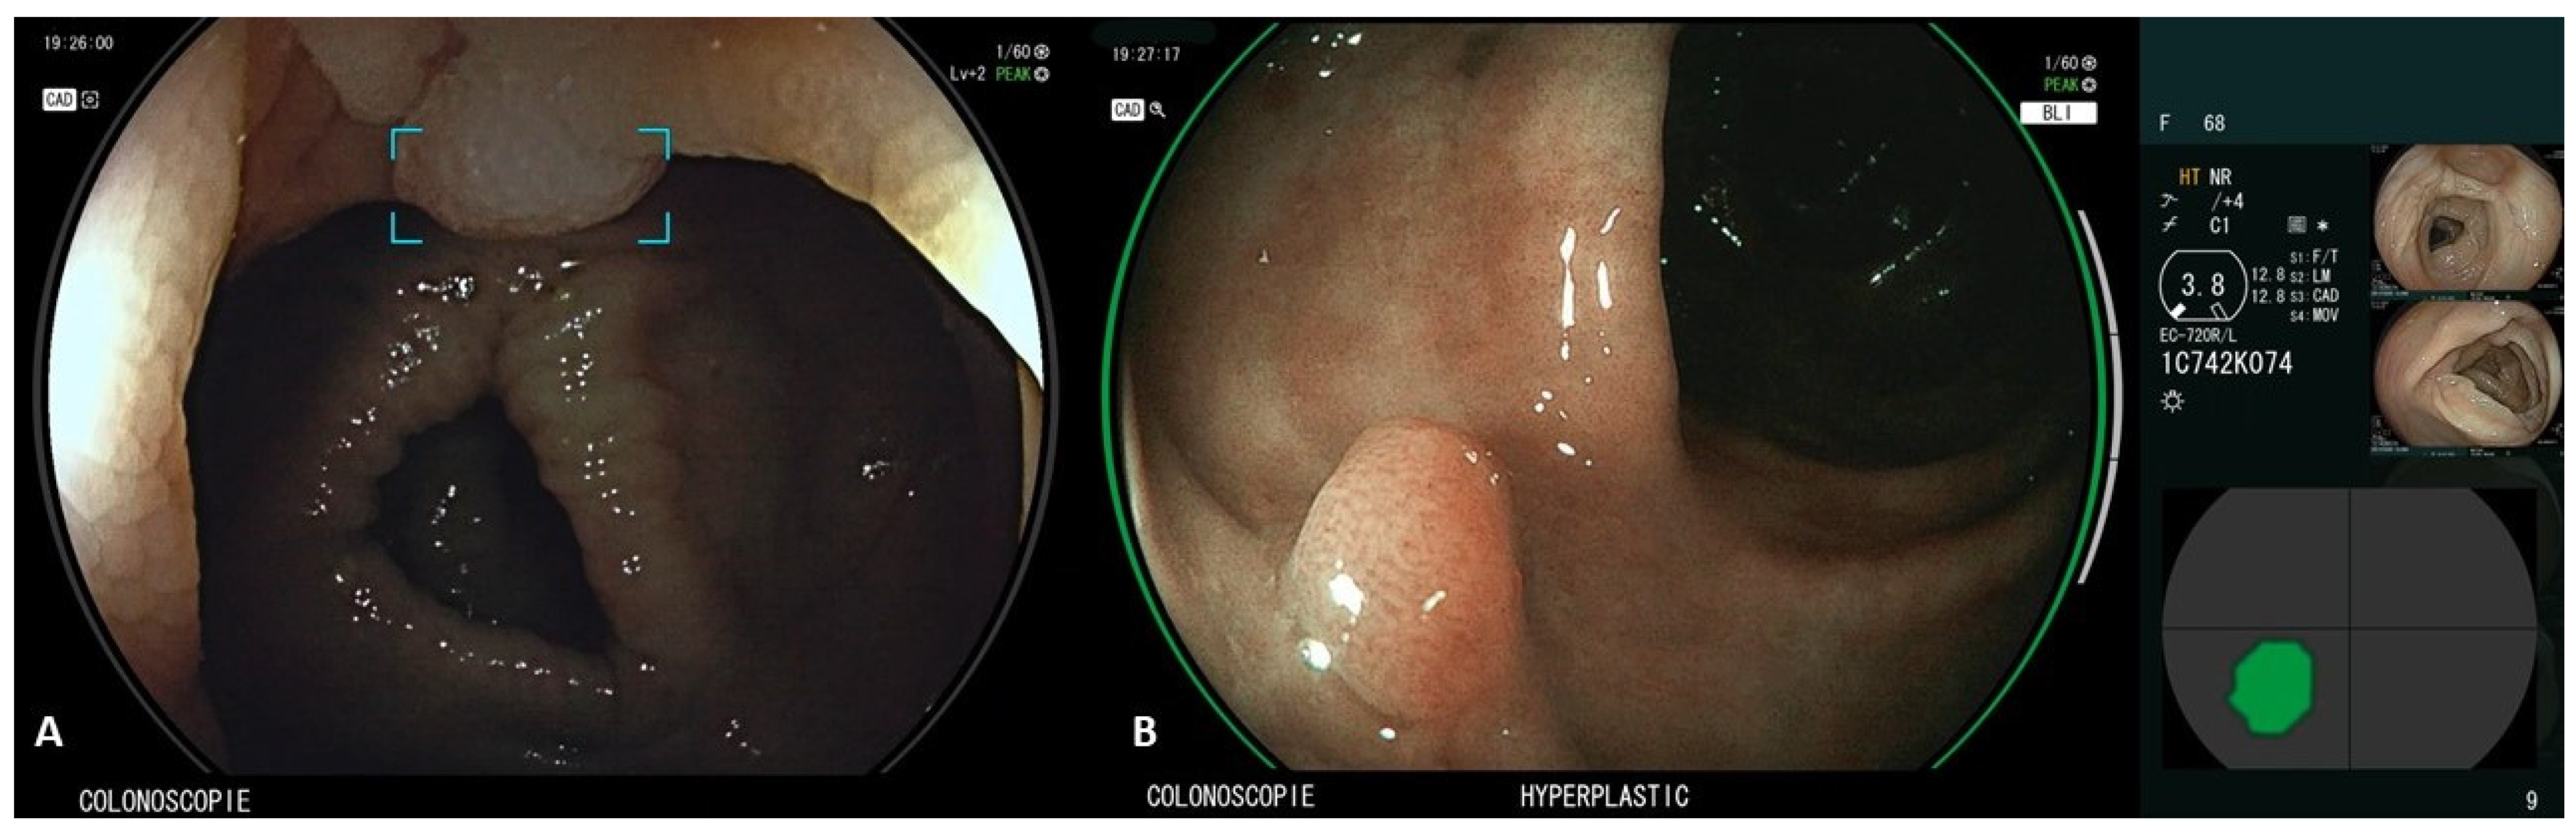

CAD EYETM (Fujifilm, Tokyo, Japan) is the first CAD system to combine computer-aided detection (CADe), which detects gastrointestinal lesions, and computer-aided diagnosis (CADx), which characterizes gastrointestinal lesions on the same platform (Figure 2), demonstrating a better performance than the human eye [12]. CADe uses LCI to enlighten differences in color in the red zone and CADx uses BLI, which varies the light emission ratios of multiple lights with different wavelengths to distinguish polyps by intensifying minute vessels and structures in the mucosa [13]. A retrospective trial of colorectal polyps evaluated its effectiveness by using endoscopic images obtained from seven centers as validation images. The detection sensitivities of white light imaging (WLI) and linked color imaging (LCI) for the CADe system were 94.5% and 96%. The accuracy of WLI and blue light imaging (BLI) in CADx was 93.2% and 94.9% [12]. However, to date, the CAD EYE system can only be used to evaluate colorectal lesions, which it can only classify as neoplastic or hyperplastic, with further applications currently under development (such as diagnosis of cancer invasion depth, prediction of metastasis, and recurrence) [14].

Figure 2.

CAD EYETM Software (Fujifilm, Tokyo, Japan); panel (A)—CADe function. A polyp is identified in WLI and marked using an annotation box; panel (B)—CADx function. The polyp is evaluated by CAD EYE in BLI and a diagnosis of hyperplastic polyp is indicated at the bottom of the monitor screen. The position and outline of the polyp is also indicated in the lower right part of the monitor.